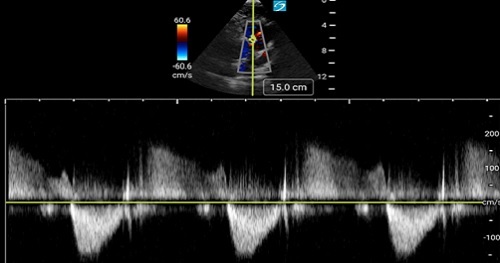

Doppler echocardiography is the language of flow in and around the heart. In order to evaluate hemodynamics in and around cardiac valves, cardiac pressures or in the calculation of Stroke Volume (SV), one must speak the language of Doppler.

This introduction to Doppler principles and how they relate to point-of-care echocardiography will frame the knowledge you need to engage some particularly valuable hemodynamic techniques!